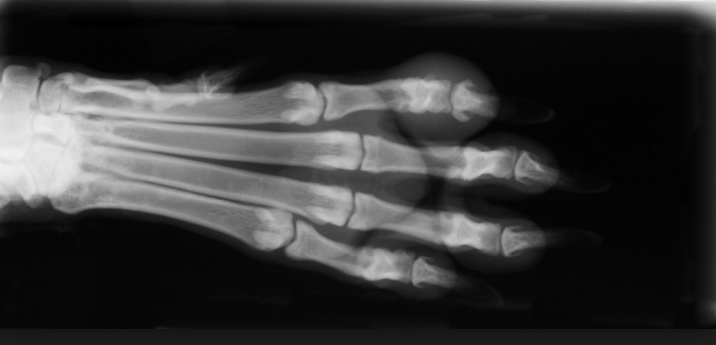

Louise — continued her (untitled) “work memoir” about being a radiologist in a small country hospital. Originally the department had a photographic dark-room, with an near-religious temple-ritual about entering it. Thanks to the head of the department keeping in with the local vets, X-rays of dogs’ paws and horse’s hooves were often to be found among the human images. Then an all-in developing machine arrived, and everything became so much simpler, and far more boring. Gone was the possibility of rescuing an over-faint negative from the developing dish. The animal limbs still occasionally show up, however.